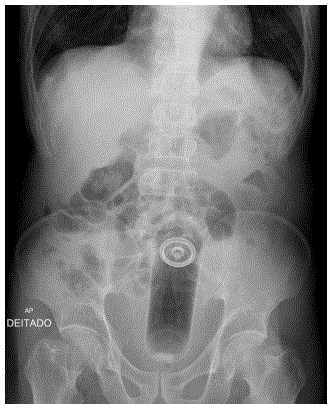

• Solicitado exame de imagem (RX abdome) mostrado ao lado.

Qual é a abordagem mais indicada a ser realizada a seguir, com base nos dados clínicos e no exame de imagem?